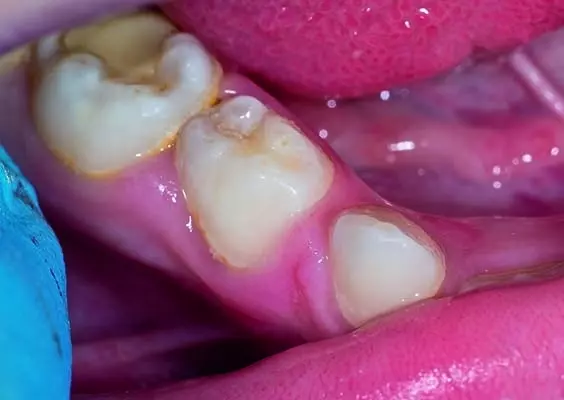

Periodontopatie należą do najczęściej występujących stanów zapalnych u ludzi i podobnie jak cukrzyca czy otyłość są obecnie zaliczane do chorób społecznych. Postawienie trafnej diagnozy dotyczącej stanu przyzębia powinno ułatwić opracowanie zindywidualizowanego programu profilaktycznego lub planu leczenia zarówno w praktyce ogólnostomatologicznej, jak i w praktyce specjalistycznej.

Postawienie trafnej diagnozy dotyczącej stanu przyzębia powinno ułatwić opracowanie zindywidualizowanego programu profilaktycznego lub planu leczenia zarówno w praktyce ogólnostomatologicznej, jak i w praktyce specjalistycznej. Działanie takie zostało określone jednym z kluczowych celów dla poprawy zdrowia przyzębia ogółu populacji w niedawno opublikowanym globalnym wezwaniu do działania zatwierdzonym przez czterdzieści profesjonalnych organizacji zajmujących się chorobami przyzębia (Tonetti, Jepsen, Jin i Otomo-Corgel, 2017). Podejście to uwzględnia cztery ustalone etapy diagnostyczne, które należy przejść sekwencyjnie, jak również zawiera narzędzia diagnostyczne i algorytmy decyzyjne potrzebne do właściwej oceny zdrowia przyzębia, postawienia rozpoznania oraz leczenia. Pierwszym krokiem jest wysoce czułe badanie przesiewowe oparte na identyfikacji obecności lub braku utraty CAL (Clinical Attachment Level) lub kości (Bone Loss – BL) na podstawie radiogramów. Etap ten umożliwia wybór użycia radiografów o odpowiedniej jakości diagnostycznej lub CAL jako parametru umożliwiającego podejrzewanie występowania zapalenia przyzębia, w przypadku braku badania radiologicznego. W przypadku stwierdzenia utraty kości wyrostka zęb...